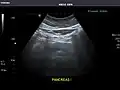

Pancreas: Visualized portions unremarkable.

Ultrasound can be used for additional anatomical information for patients with an abnormal kidney function or pancreatic enzymes (pancreatic amylase and pancreatic lipase).